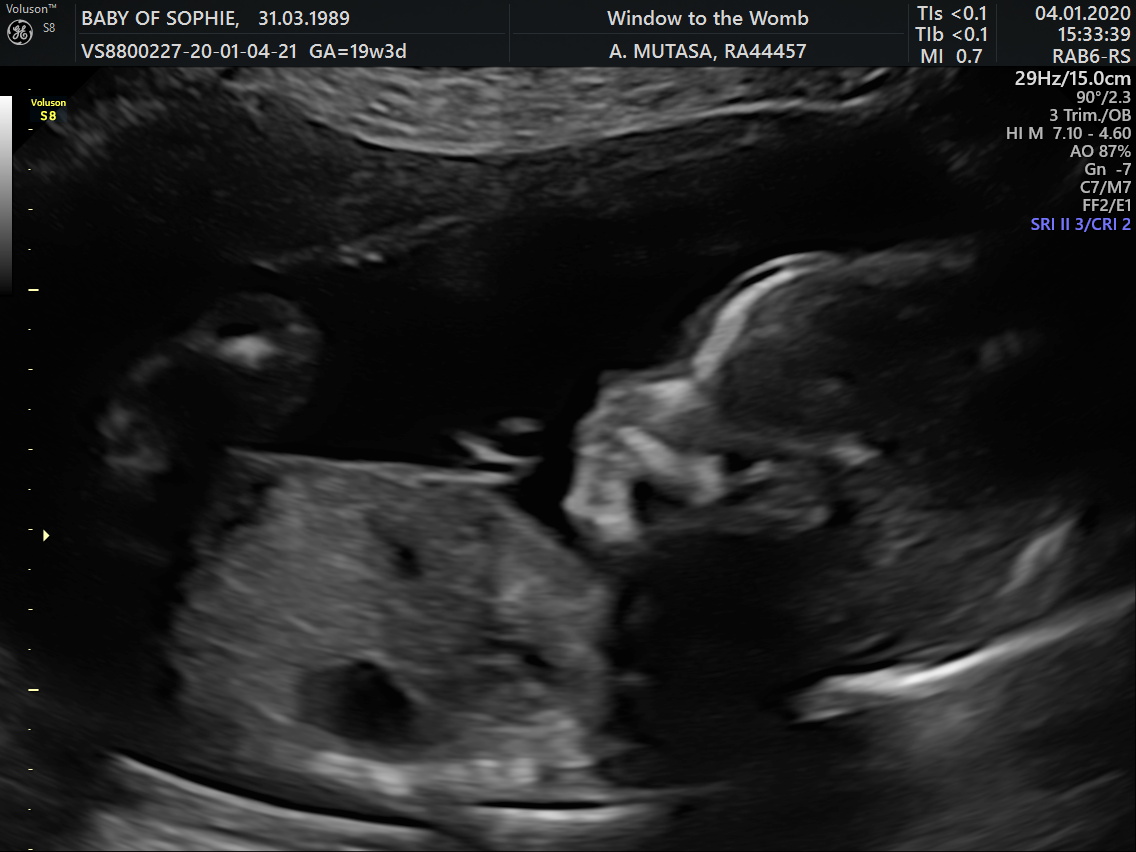

Bottom pic from 12 week scan